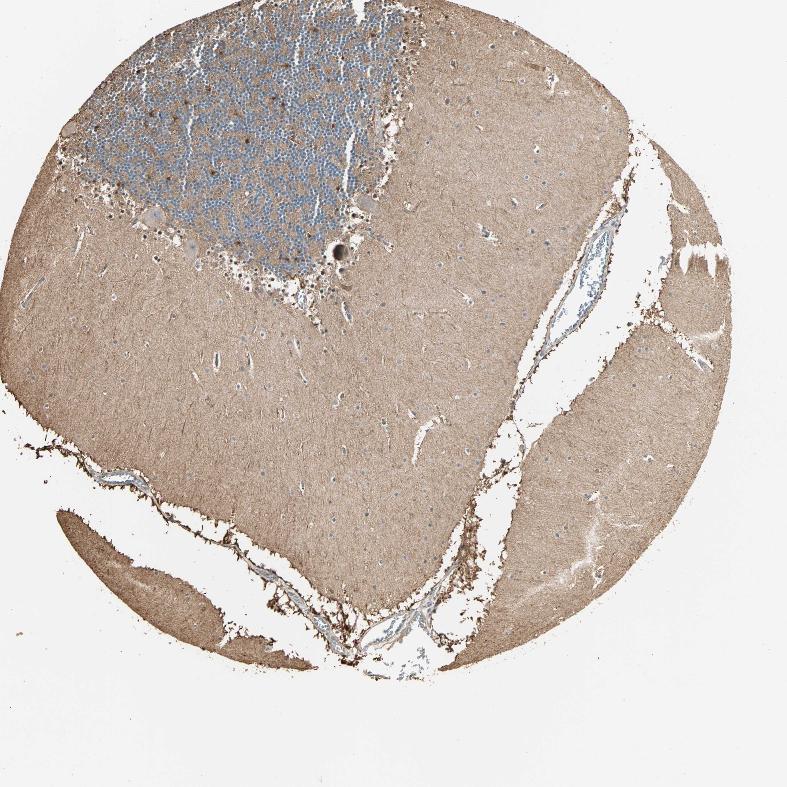

CEREBELLUM - Antibody stainingi

Antibody staining in the annotated cell types in the current human tissue is reported as not detected, low, medium, or high, based on conventional immunohistochemistry profiling in selected tissues. This score is based on the combination of the staining intensity and fraction of stained cells.

Each image is clickable and will lead to virtual microscopy that enables deeper exploration of all samples and also displays staining intensity scores, fraction scores and subcellular localization as well as patient and tissue information for each sample.

Antibody HPA007716

Purkinje cells Low

Cells in granular layer Not detected

Cells in molecular layer Low